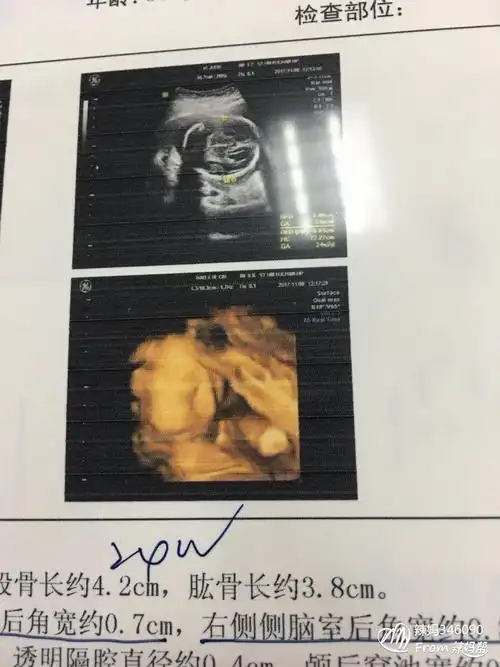

怀七个月做的四维,哈哈,宝妈们看看这是男孩女孩